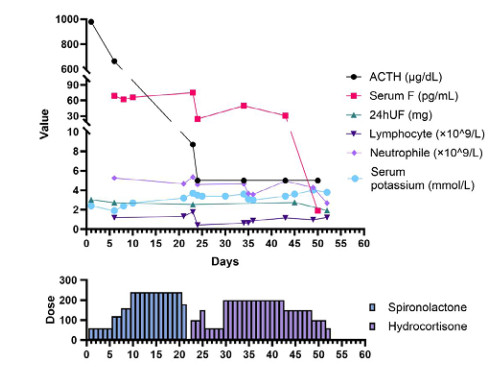

第一次收住院诊疗经过:完善常规生化提示低钾血症、高脂血症,超声心动图:微量心包积液,EF67%。肺通气功能正常。库欣综合征定性定位诊断方面,血总皮质醇(血F)(8AM) 69.6 μg/dL, ACTH(8AM) 664.0 pg/mL, 24 h尿游离皮质醇(24HUFC)2 723.2 μg/24 h,大剂量地塞米松抑制试验(见表 1); 标筛查:AFP 4.6 ng/mL, CA19-9 22.2 U/mL, CEA 3.0 ng/mL, CA125 38.4 U/mL, 细胞角蛋白19片段Cyfra211 6.0 ng/mL, CA242 19.0 U/mL, CA72-4 8.6 U/mL, CA15-3 12.9 U/mL, ProGRP 26.0 pg/mL, NSE 15.4 ng/mL。生长抑素受体显像:前纵隔结节,生长抑素受体高表达灶,考虑神经内分泌肿瘤可能性大;双侧肾上腺增生。(图 1C);垂体平扫+动态增强MRI:垂体后叶短T1信号存在垂体左翼强化减低区,考虑微腺瘤。胸增强CT:前纵隔占位,结合病史,不除外异位ACTH瘤(图 1A);TB细胞亚群11项: %memory T4 78.1%, B% 17.9%, T4% 17.6%, T8% 42.1%, RAT4% 21.9%, NaT4% 21.7%, 28T8% 32.1%, DRT 8% 76.2%, 38T8% 83.0%, T4/T8 0.42%, 垂体前叶功能,甲功1:TSH 0.077 μIU/mL, FT4 1.73 ng/dl, FT3 2.17 pg/mL, GH < 0.05 ng/mL, IGF1 132 ng/mL。FSH 2.13 IU/L, LH 0.26 IU/L, E2(Ⅱ) < 15 pg/mL, T 1.96 ng/mL, PRL 6.9 ng/mL, P 5.31 ng/mL。MEN筛查,GASTRIN 260 pg/m,ProGRP 23.9 pg/mL。降钙素(CT) < 1.5 pg/mL,钙素原PCT 0.23 ng/mL, CK 33 U/L。IPSS+DDAVP兴奋试验示基线时中枢和外周ACTH无梯度(见表 2),结合大剂量地塞米松抑制实验不被抑制,支持异位ACTH综合征,考虑胸腺占位为责任病灶可能。治疗方面,入院后予口服及静脉补钾、螺内酯纠正低钾血症,监测血糖,餐后2 h血糖高,给予胰岛素及口服降糖药后血糖基本达标。患者前纵隔结节考虑为异位ACTH瘤可能大,2020-08-26行VATS胸腺及肿瘤切除术,术后恢复良好,激素替代方案由围术期静脉应用琥珀酸氢化可的松逐渐过渡为醋酸氢化可的松片早40 mg,晚20 mg替代治疗后出院(图 3主要指标趋势及用药情况)。2020-08-31无明显诱因出现发热,体温最高达39℃,当地诊所静点“头孢类抗生素”、口服布洛芬治疗2 d,仍间断发热,并出现站立后头晕,当时血压76/40 mmHg,就诊当地医院,查血常规:WBC 6.01×109/L, NEUT% 85.2%, LYM% 13%; CRP 194.74 mg/L; CMV DNA阳性;胸部CT提示双肺弥漫渗出,考虑“重症肺炎I型呼吸衰竭”于当地重症监护室予以“无创呼吸机辅助呼吸,哌拉西林他唑巴坦、奥司他韦、伏立康唑抗感染,丙种球蛋白免疫支持”。治疗效果欠佳,胸闷、憋气逐渐加重,伴咳少许白色黏痰。2020-09-03就诊本院,考虑重症肺炎收入急诊重症监护病房,第2次收住院诊疗经过:呼吸方面:复查胸CT提示:双肺弥漫炎性改变,双侧胸腔积液并左下肺轻度膨胀不全(图 2A 、B)。予高流量氧疗支持,完善肺泡灌洗液: PCP DNA阳性(+),CMV(+),结合病史、症状、体征及辅助检查证据,考虑肺孢子菌肺炎、巨细胞病毒肺炎、混合细菌感染,头孢他啶1 g/8 h、莫西沙星0.4 g/d、TMP/SMX 3片3次/d,更昔洛韦0.25 g/8 h,呼吸困难逐渐改善,复查CT病灶明显吸收(图 2C 、D)。内分泌方面:考虑EA导致CS术后,激素替代治疗中合并机会性感染,调整治疗:停用口服,给予琥珀酸氢化可的松50 mg/6 h。口服降糖药控制类固醇糖尿病,口服碳酸钙片治疗骨质疏松。原发病方面:结合病理胸腺病灶考虑内分泌来源类癌,恶性程度低,无需放化疗。2020-09-30出院时患者无发热、头晕、纳差、恶心、呕吐、电解质紊乱、低血糖等肾上腺皮质功能不全表现,氢化可的松早40 mg-午20 mg逐渐减量(图 3主要指标趋势及用药情况),激素替代期间TMP/SMX 2片/d预防感染,门诊随诊。

| 图 3 血促肾上腺皮质激素(ACTH)、血总皮质醇(serum F)、24 h尿皮质醇(24UF)、淋巴细胞绝对值(lymphocyte)、中性粒细胞绝对值(neutrophile)、血清钾离子水平(serum potassium)趋势及螺内酯(spironolactone)、氢化可的松(hydrocortisone)的用量关系图 |

原发病治疗:异位ACTH最佳治疗方案为手术切除肿瘤,从而去除ACTH来缘,Isidori等[4]报道的26例肺类癌患者中10例在切除肿瘤后病情缓解,9例局限性神经内分泌肿瘤或其他类癌患者中有8例在切除肿瘤后获得缓解对于肿瘤无法切除的患者可使用肾上腺酶抑制剂来控制皮质醇增多症,如酮康唑、美替拉酮和依托咪酯等,可以通过抑制一种或多种皮质醇合酶发挥作用。本例患者经过术前评估,符合可切除肿瘤,结合图 3 ACTH变化趋势可以看出,原发病方面手术效果良好,但围手术期的激素替代方案需要充分的经验及密切的监测才能避免出现皮质功能不全甚至肾上腺危象的出现。

并发症评估处理:该患者目前突出的表现为中-重度低钾血症,考虑为大量皮质醇激动盐皮质激素受体所致。密切监测血钾,积极纠正低钾血症,警惕低钾血症所致的心律失常、横纹肌溶解。患者首次住院期间出现严重低钾血症,经过大量的口服及静脉补钾增加钾的摄入,螺内酯保利尿剂增加钾的重吸收,具体剂量及治疗反映详见图 3,是保障患者尽快诊断及治疗的重点难点所在。皮质醇血症可导致糖脂代谢、水盐平衡异常,可通过监测血糖、HbA1c、糖化白蛋白、容量管理等动态调整,有研究表明,液体负平衡可降低重症肺炎患者病死率[5]。钙磷代谢方面,长期高皮质醇血症可促进尿钙排泄、抑制肠钙吸收,导致继发性骨质疏松,因此骨密度、胸腰椎正侧位等检查及积极补钙等治疗是预防骨质疏松防止骨折的关键。通过完整的定性定位检查及手术病理证实为前纵隔类癌的EA所致CS,整个病程相对较长,虽手术过程顺利,但术后激素替代过程中很快出现了机会感染,结合图 3趋势不难发现,患者术后ACTH及血F水平急剧下降,淋巴细胞绝对值也低于正常下限,当内源性激素水平迅速下降的同时,外源性激素补充不及时可能出现皮质功能不全表现,且患者体内长期处于高皮质醇水平,加之手术打击,再次发热后迅速出现多种机会病原体感染,PCP及巨细胞病毒(cytomegalovirus,CMV),内环境紊乱、皮质功能不全进展为休克,病情危重,病死率极高,因此,机会性感染的早期识别、合理的抗感染方案及容量管理策略至关重要[6]。

2.3 为什么药物控制或手术切除肿瘤后患者容易发生机会性感染?Arlt, A报道的右肾神经内分泌肿瘤患者在接受甲吡酮和氢化可的松治疗,皮质醇水平下降后肺泡灌洗液发现PCP,虽加用预防性复方磺胺甲恶唑治疗仍迅速进展为呼吸衰竭死亡[7],Graham等[8]曾报道6例内源性库欣综合征合并机会性感染,感染风险与皮质醇水平相关,Sarlis等[9]回顾性分析发现,当皮质醇水平下降过程中继发重症PCP感染,可能与氢化可的松的抗炎作用减低有关;van Halem等[10]系统回顾了库欣合并PCP感染患者,发现在开始应用肾上腺抑制剂如酮康唑、米托坦或糖皮质激素受体拮抗剂如米非司酮等治疗使皮质醇水平下降时,在激素替代的免疫重建过程中也容易继发PCP等机会感染,Hasenmajer等[11]在近期的一篇库欣综合征与免疫的综述中提到,当通过药物或手术使患者库欣得到缓解时,患者体内淋巴细胞计数会随之下降,可能与过程中影响骨髓造血、细胞因子变化及免疫细胞凋亡相关,进而使机会感染风险增加,这点与本文患者表现一致(图 3)。另文献报道,当24 h尿UFC超过5倍上限或血皮质醇水平超出正常上限20倍时,或者治疗后存在激素水平急剧下降时,此时建议经验性加用复方磺胺甲恶唑预防机会性感染[12]。